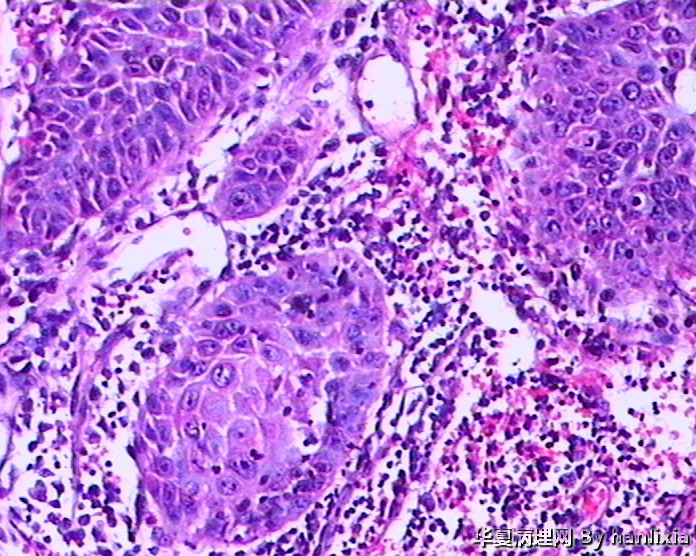

男性患者,50岁,发现面部皮肤(耳旁)肿物一年余,色黑。

高分化鳞状细胞癌

高分化鳞癌可能,也可能AK基础上发展而来的浅表型鳞癌?

部分区域突破基底膜,应该诊断鳞癌,由日光性角化发展过来的!